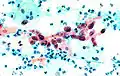

- Zytologische Befunde und histologischer Befund in Papanicolaou-Färbung

-

Normale Plattenepithelzellen im Abstrich

Normale Plattenepithelzellen im Abstrich -

Atypische Zelle im Abstrich (Mitte)

-

Plattenepithelkarzinom (histologischer Schnitt)

Plattenepithelkarzinom (histologischer Schnitt)